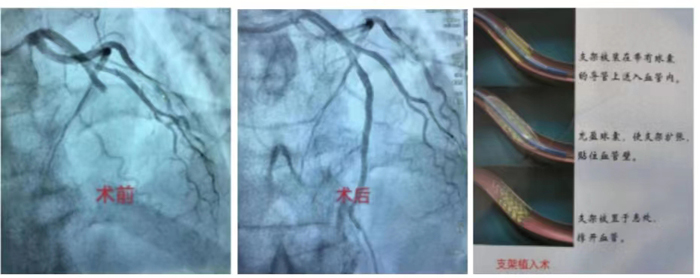

冠心病介入诊疗技术:科室常规开展冠状动脉造影术、经皮冠状动脉球囊扩张术(PTCA)、经皮冠状动脉药物球囊扩张术,振波球囊技术治疗冠脉严重钙化病变、冠状动脉支架置入术、心脏血管内超声检查(IVUS)、血流储备分数测定(FFR)、冠状动脉旋磨成形术等介入手术。在冠脉左主干、分叉病变、慢性完全性堵塞性病变、弥漫性及钙化病变等复杂病变方面积累了丰富的经验。胸痛中心针对急性心肌梗死患者开通绿色通道,其中急诊冠心病介入诊疗技术为枣庄地区开展最早,挽救急性心肌梗死病人最多的科室。

急诊PCI术:是指在患者发生急性心肌梗塞后12小时内进行的冠状动脉血运重建,患者首先在导管室行冠状动脉造影术,找出冠状动脉“罪犯”血管及其病变部位,对病变部位行经皮冠状动脉腔内成形术和植入支架,使闭塞的血管得以再通,梗死相关心肌得以及早的再灌注和功能恢复。可以说,急诊PCI术为挽救急性心梗垂危的生命在最短的时间内构建了一条绿色的通道,提高危重症患者的抢救成功,使急性心肌梗死的死亡率下降,提高患者的生活质量。因此,在急性心肌梗死的时间窗内,介入治疗已是首选治疗手段,其急诊PCI大大降低死亡率及心肌梗死并发症,提高生存率及改善生活质量。